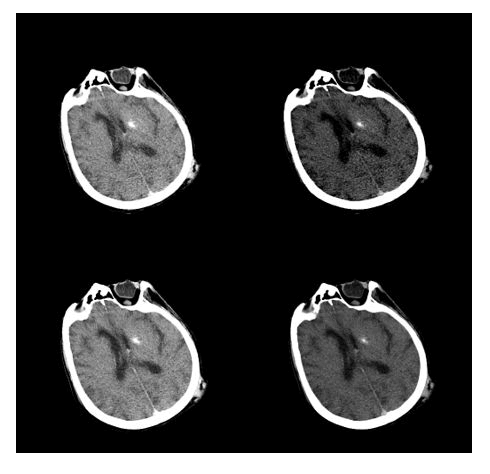

Take, for example, Figure 9, where the same image from four different acquisition sets is compared. In this case, three CT scans of the chest were performed on an 82-year-old deceased individual. The scanning parameters were kept the same for all three packages, except for the different kilovoltage values: 80 KV, 100 KV and 120 KV. Finally, a fused CT reconstruction was performed by summing the raw data from all the acquisitions.

As observed previously, there is a decrease in the absolute value of noise with increasing KV values, resulting in improved spatial resolution and clarity in identifying the boundaries of various structures. However, visually, there is a perceived flattening due to the decrease in contrast resolution.

Focusing on the origin of the ascending aorta, we can see how the issues identified with the other datasets are mitigated with the fusion CT technique: The vessel profile becomes sharp and well-defined, the contrast between the vessel lumen and surrounding tissues is enhanced and the noise is drastically reduced.

Figure 9. Comparison of images of the mediastinum with fusion CT and acquisitions at different energies: Respectively 80 KV (top left), 100 KV (top right), 120 KV (bottom left) and fusion CT reconstruction of the previous (bottom right).